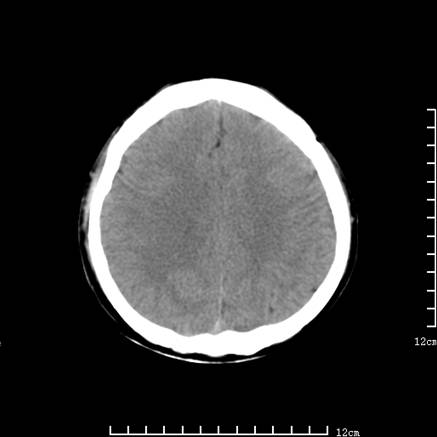

以下是引用jiajie在2008-9-5 22:25:00的发言:[br]男,22岁,头痛1月余。脑室、脑池内病变ct值约-120hu。[br][br]双侧侧脑室内低密度影充填,出现脑脊液脂肪平面,脑池内亦可见弥散分布的斑点状低密度影,脑室脑池未见明显扩大。[br]考虑胆脂瘤破裂后内容物进入脑脊液。